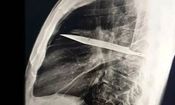

• کشف عجیب در قفسه سینه؛ چاقویی که ۸ سال در بدن مردی جا خوش کرده بود

کشف عجیب در قفسه سینه؛ چاقویی که ۸ سال در بدن مردی جا خوش کرده بود